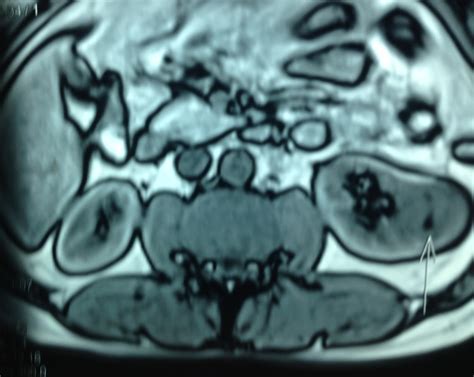

A Kidney AML tumor is a type of mesenchymal tumor, which means it arises from the soft tissues of the kidney rather than the filtering units themselves. Because these tumors contain fat, they have a unique appearance on medical imaging tests like CT scans or MRIs, which helps radiologists distinguish them from potentially cancerous kidney tumors. Most angiomyolipomas occur sporadically, meaning they appear spontaneously without a clear hereditary link. However, a significant subset of patients develops these tumors in association with a genetic disorder known as Tuberous Sclerosis Complex (TSC). In patients with TSC, these tumors are often more numerous, larger, and more likely to affect both kidneys.

Diagnosing a Kidney AML tumor involves various imaging modalities to assess the size and character of the lesion. A CT scan with contrast or an MRI is typically the gold standard because these scans can identify the presence of fat within the tumor—a hallmark characteristic of an angiomyolipoma.